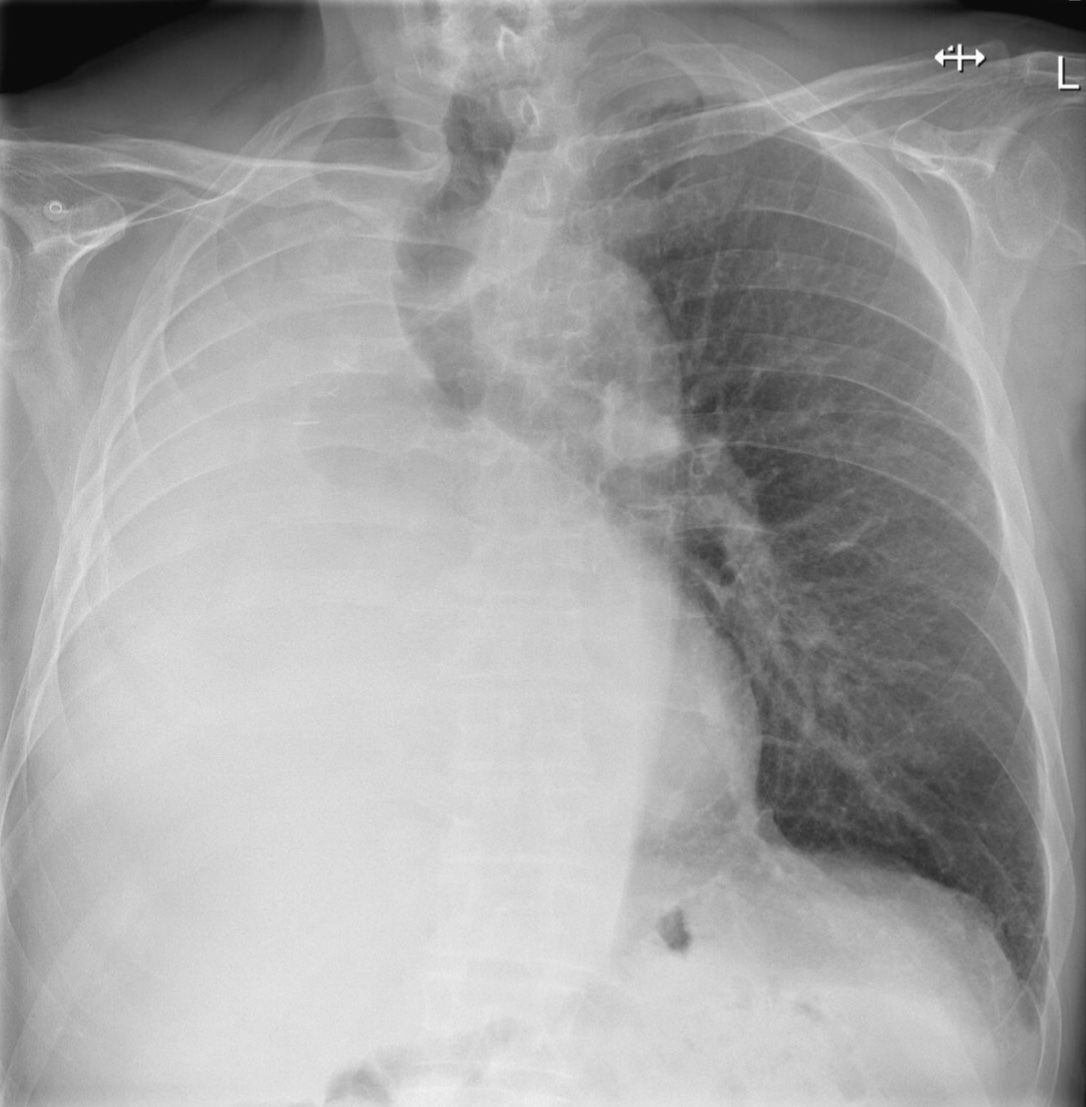

Unilateral pleural effusion